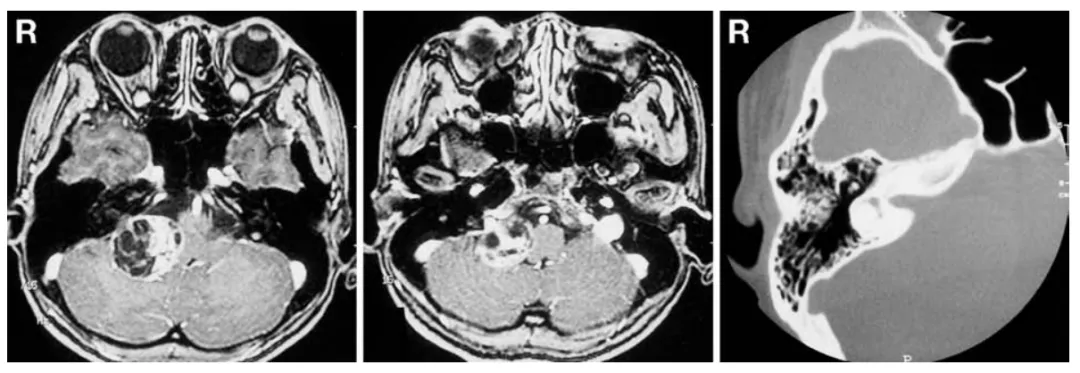

29岁的小葵,因听力丧失就诊,无其他神经功能缺损。初次磁共振成像显示,右侧桥小脑角区存在一直径3.5厘米的囊实性强化占位病变,压迫脑干,但未见明显侵犯内耳道或颈静脉孔(图1左、中)。骨窗计算机断层扫描未见内耳道明显扩大(图1右)。

图1术前轴位增强T1加权磁共振成像(左、中)显示,右侧桥小脑角区占位性病变,未明显侵犯颈静脉孔。术前骨窗计算机断层扫描(右)显示,内耳道无明显扩张。